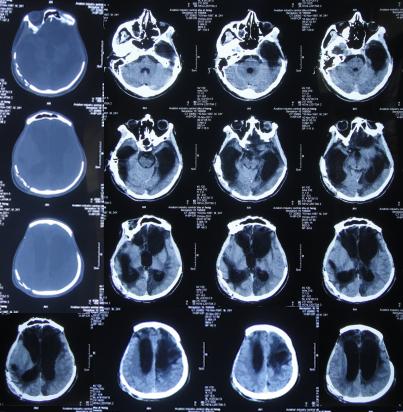

第4家医院治疗87天即开颅术后289天即2011年10月31日,因脑积水始终未得到满意治疗;期间还外请更高级的北京某三甲知名医院的专家会诊,但此专家看完头颅CT后( 图-8 )建议暂时不做腹腔分流术,因为他断定:“做了分流术之后,患者也不可能好转!”。

图-8: 2011年10月31日头颅CT

入院时:昏迷状态,刺激无发音,能自动睁眼但肢体不能遵嘱动作,不能吞咽吃饭。头部情况:双侧额颞部去骨瓣减压术后颅骨缺损,头皮手术瘢痕未见异常渗出,骨窗大小约7*8cm,头皮凹陷;头颅CT(外院2011年10月31日)提示脑外伤术后,脑积水。但右侧原手术刀口经久近1年不愈合,以往几家医院均认为除了自愈之外没有好的治疗方法。